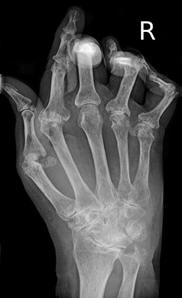

Normal hand RA - Damaged finger joints RA - Fused finger joint

Normal hand bones RA - Damaged hand bones RA - Damaged hand

https://commons.wikimedia.org/wiki/File:RheumatoideArthritisAP.jpg

Description   Typisches Röntgenbild einer

Rheumatoiden Arthritis.

Description English:

X-ray of right fourth proximal

interphalangeal (PIP) joint with bone erosions by rheumatoid arthritis. Taken October 2002. Same joint is partially healed on a follow-up X-ray

after treatment with conventional disease-modifying

antirheumatic drugs(DMARDs) one year later: File:X-ray of right fourth PIP joint with partially healed bone erosions by

rheumatoid arthritis.jpg